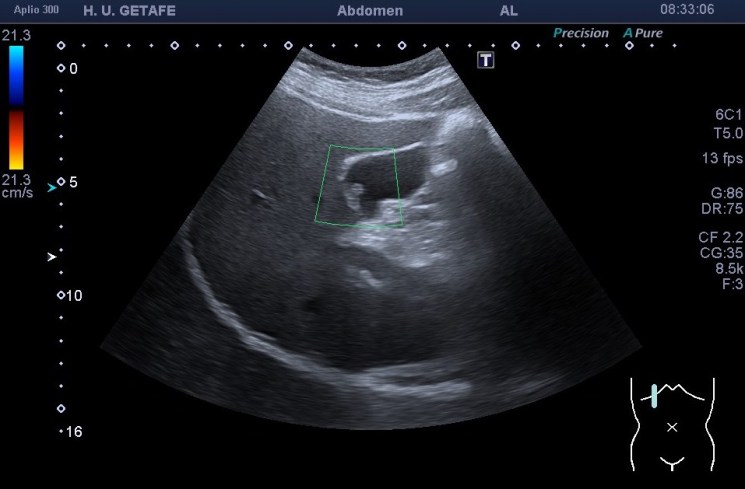

El estudio del pólipo tras su localización se realiza en dos proyecciones, variando al paciente de posición para ver si se mueve. Ponemos doppler, tanto color como modo angio, con el objetivo de demostrar un vaso en el interior del pólipo, que lo delataría como una estructura de aspecto maligno y debería ser valorado por el radiólogo y por el cirujano convenientemente. Por eso ajustar el doppler es muy importante en este caso también.

Medimos para hacer seguimiento de la lesión si se requiriese así. Aplicamos zoom para estudiarlo detalladamente, a mi me encantan las imágenes en este Canon. El Zoom es muy bueno y el estudio del pólipo gana muchísimo. Hablando del Zoom…

Como muy bien puedes observar el caso es bastante anodino, las imágenes te las he puesto y son la excusa para explicarte el uso del Zoom. Habitualmente es un ajuste ecográfico que no usamos en exceso, solo puntualmente, puede pixelar en exceso la imagen, como cuando hacemos una foto con nuestro móvil y la ampliamos con el gesto de nuestros dedos…pixelamos la imagen, perdemos resolución, pero lo nuevos equipos, ganan en esto también y con las sondas de baja frecuencia podemos conseguir imágenes muy bonitas de alguna ecoestructura pequeña y que nos interese medir bien, y este caso me resultó muy plástico y te lo quería explicar. Repasamos el concepto de pólipo vesicular y lo enlazamos con el uso del zoom.

Te animo que uses este ajuste o función del equipo para estudiar algunas estructuras pequeñas que desees ampliar aunque pierdas el detalle de aquellas estructuras que tenemos alrededor y que en ese caso no te resulten interesantes para esa foto que quiera documentar.